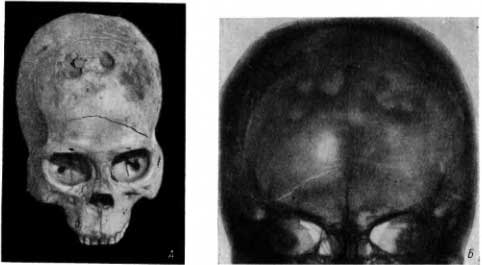

На черепе человека, жившего в первые века нашей эры (из раскопок С. А. Теплоухова в Туве), мы обнаружили на левой теменной кости крупную окостеневшую сифилитическую гумму в виде части шара, с диаметром основания около 12 мм (рис. 34, А).

Рис. 34. А — окостеневшая крупная сифилитическая гумма на теменном кости; Б — 2 типичных участка гуммозной сифилитической деструкции на теменной кости.

На черепе одного из убитых в 1241 г. в Изяславле (см. главу IV, 10) в левой теменной кости имелось 2 рядом расположенных, круглых участка деструкции. Разрушены были лишь наружная пластинка черепного свода и примыкавшая к ним губчатая структура. Имелся слабо выраженный периостальный ободок на наружной пластинке (рис. 34, Б).

Такие же гуммозные поражения черепного свода у значительного количества людей близких нам времен описал Вирхов. Он подчеркивал, что при гуммозных сифилитических поражениях черепа больше всего поражается наружная пластинка, в меньшей мере — губчатое вещество и внутренняя пластинка черепного свода. Часто на большом материале Вирхова деструкция ограничивалась только наружной пластинкой. Как уже отмечалось, Вирхов, описавший эти характерные особенности сифилитических гумм на черепе, отрицал древность этого заболевания.

На костях мозгового черепа, на наружной пластинке главным образом лобной и теменных костей, видны окостеневшие сифилитические гуммы в виде шишковидных бляшек (рис. 36, А). Эти сифилитические бляшки легко увидеть: они более блестящие и светлые, более белые, чем соседние нормальные участки кости. На глаз структура этих сифилитических бляшек однообразнее окружающей нормальной кости. В рентгеновском изображении эти бляшки, как крупные, так и мелкие, отличались отчетливо выраженным склерозом и бесструктурностью (рис. 36, Б). Располагаясь поверхностно на наружной пластинке черепного свода, они, естественно, могут быть обнаружены в рентгеновском изображении только тогда когда являются краеобразующими.

Рис. 36. А — множественные окостеневшие сифилитические гуммы различной величины; Б — окостеневшая сифилитическая гумма черепного свода в рентгеновском изображении (в краеобразующей зоне).

В значительном числе случаев наблюдались очень тяжелые изменения. Нередко треть свода черепа была разрушена преимущественно в его поверхностных слоях (рис. 38, А и Б).

Рис. 38. А — сифилитическая деструкция значительной поверхности черепного свода; Б — на рентгенограмме видны сливающиеся очаги деструкции, окруженные склеротическим валом.

Часть очагов деструкции имела ландкартообразный вид в результате слияния ранее изолированных очагов поражения. На рентгенограмме можно было часто обнаружить вокруг очагов деструкции склеротический вал (рис. 38, Б).